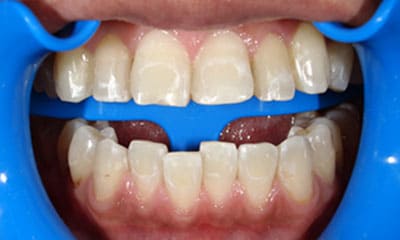

藤沢デンタルオフィスのホワイトニング術前 藤沢デンタルオフィスのホワイトニング術後

術前

術後